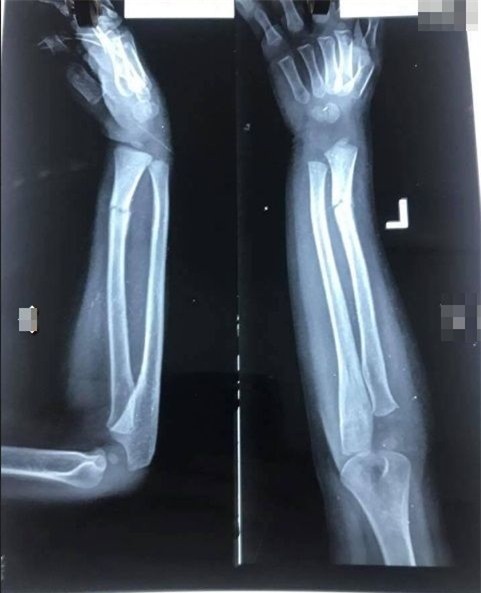

Qua những hình ảnh có thể thấy được tay trái của bé trai bị gãy phải bó bột, cùng nhiều vết lằn đỏ. Bên cạnh đó tài khoản facebook này còn cung cấp đoạn chat giữa phụ huynh cháu bé và giáo viên mầm non.